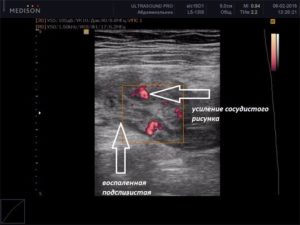

Стенка тонкой кишки состоит из слизистых оболочек, которые имеют подслизистую основу. Слизистая образует множество внутренних выростов, увеличивающих поглощение веществ в органе. Стенки также состоят из серозной и мышечной оболочек. При ультразвуковом обследовании оцениваются следующие параметры:

- наличие воспалительных процессов;

- воспалительные процессы;